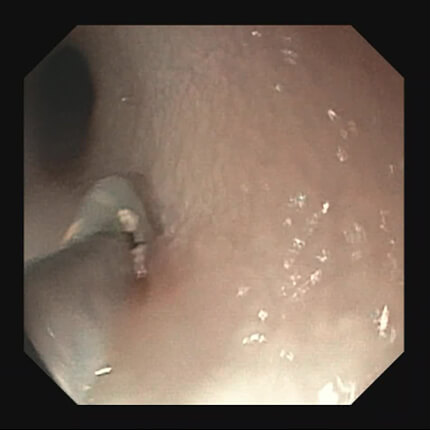

【食道】